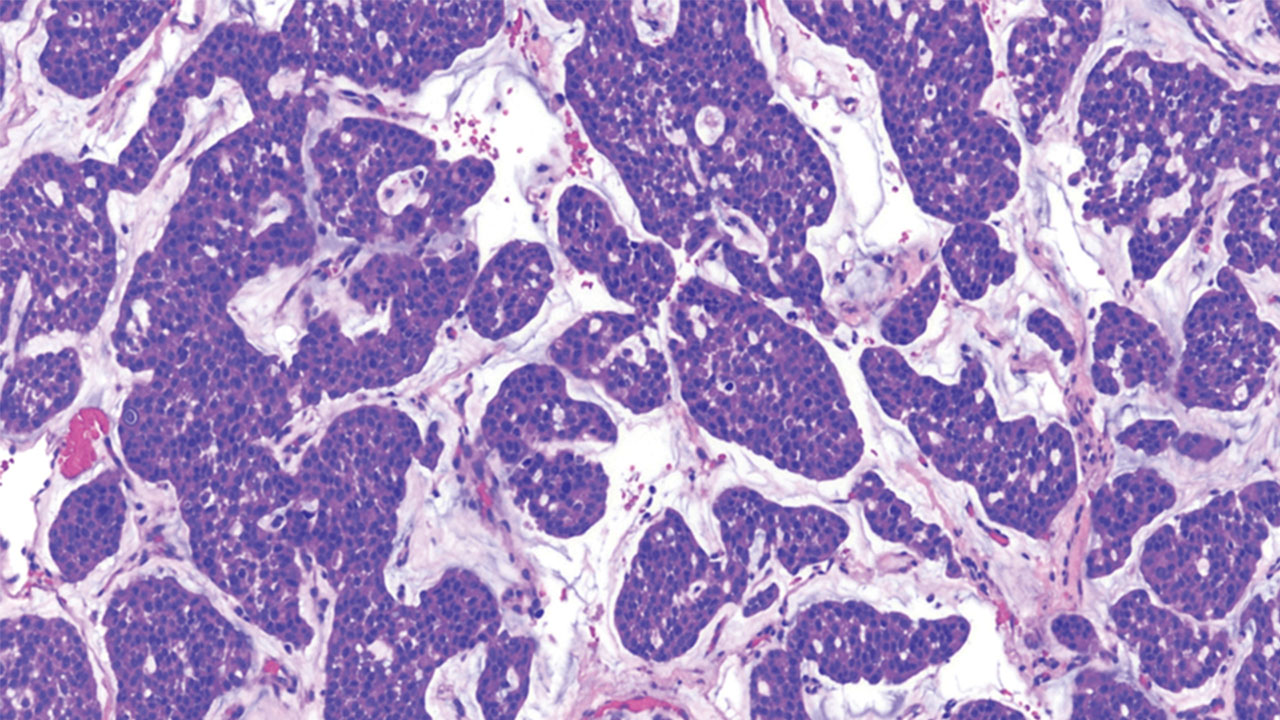

Chordomas occur in one out of one million people. The tumor cells form little bubble-like clusters and often produce a lot of cartilage-like material, seen as blue-grey areas within the tumor. They can form along the spine, invade local structures and even destroy the bones at the base of the skull or the spine. Even after surgical resection and radiation, these tumors usually keep growing back.

Chordoma under a microscope.

Chordoma